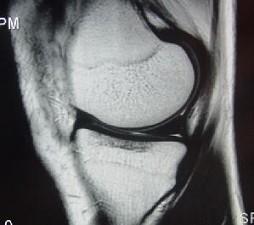

问题 男性,年龄50岁,自诉3年前有轻微的右膝关节外伤史,现感右膝关节不适,请结合所提供的图像,选择最佳选项 ( )

选项 A、左膝半月板囊变 B、左膝左膝关节积液 C、左膝关节骨关节病 D、左膝半月板损伤 E、左膝半月板退变

答案 E